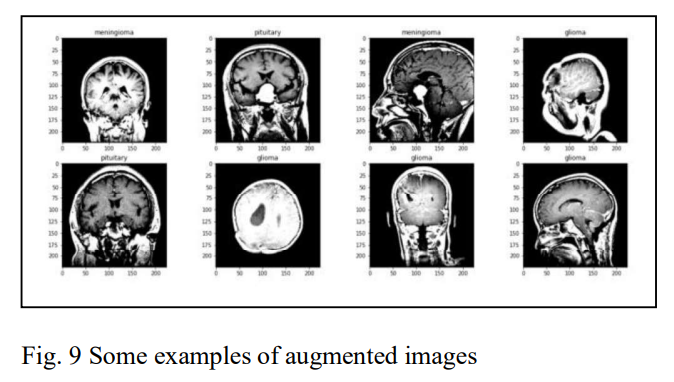

CNN+XGBoost,实现脑瘤分类。

脑瘤是大脑或中央椎管内细胞的肿块或异常生长,症状包括头痛、癫痫发作、手脚无力或麻木、性格或行为改变、恶心、呕吐、视力或听力问题和头晕。传统的脑瘤诊断涉及一些测试和程序,可能包括考虑病史、体格检查、成像测试(如CT或MRI扫描)和活检(切除和检查一小块肿瘤组织)。这些程序虽然有效,但由于对脑部扫描的人工检查和对测试结果的彻底评估在精神上很吃力,也很费时间。大量的医学研究已经证实,早期诊断和治疗的脑瘤一般倾向于有更好的预后。

深度学习技术经过多年的发展,在医学影像学中对脑瘤的分类方面已经显示出令人印象深刻和更快的结果,几乎没有人为干扰。这项研究提出了一个使用卷积神经网络(CNN)和XGBoost相结合的脑肿瘤早期检测模型。所提出的模型被命名为C-XGBoost,与纯粹的CNN相比,它的模型复杂度较低,使得它更容易训练,而且不容易出现过拟合。它还能更好地处理不平衡和非结构化的数据,这些都是现实世界医学图像分类任务中常见的问题。为了评估所提出的模型的有效性,我们采用了一个有肿瘤和无肿瘤的脑MRI图像数据集。